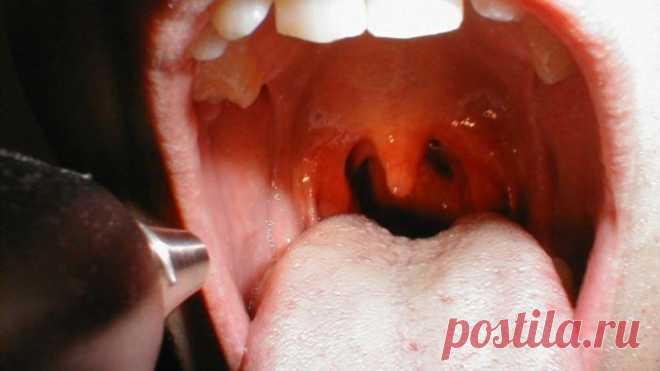

Этому трюку 400 лет и он доказал свою эффективность! В его эффективности сомневаются только те, кто не пробовал его применять! Мы применяем его всей семьёй уже много лет и он ни разу нас не подвёл! — Полезные советы